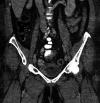

A known consequence of portal hypertension is the development of varices, which are described as "ectopic" when located at unusual sites in the abdomen. Ectopic varices carry a mortality rate as high as 40% after initial hemorrhagic episode. We report a patient who presented with hematuria secondary to bladder varices as the presenting symptom for a new diagnosis of cirrhosis. Cross-sectional imaging, early recognition of this rare event, combined with multidisciplinary management was essential for this patient to have a successful outcome.